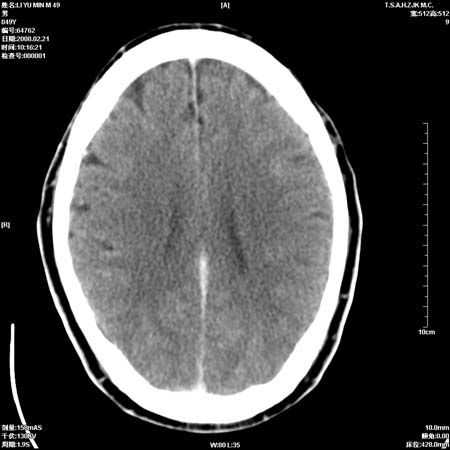

一周后复查ct:

可能为正常。间隔一周蛛血应基本吸收;再过一周复还是这样应该可以肯定了。

一周时间密度未见改变,考虑为正常图像(脑动脉硬化?)。

蛛血可能,建议短期内复查。